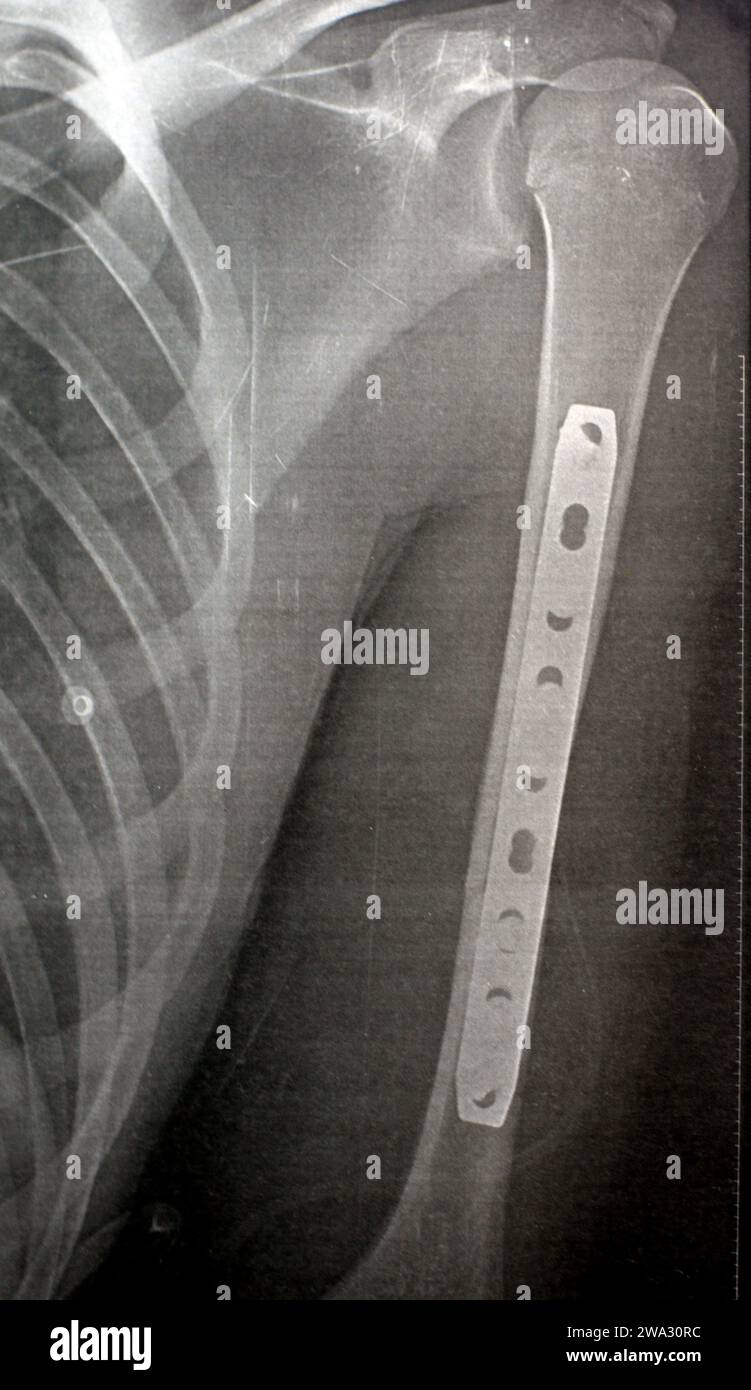

RF2WA30RC–Radiografia semplice che mostra frattura dell'omero sinistro dell'albero intermedio trasversale causata da un trauma diretto in un incidente stradale, gestito da riduzione aperta e fissa interna

RF2W9YW73–Radiografia semplice che mostra frattura dell'omero sinistro dell'albero intermedio trasversale causata da un trauma diretto in un incidente stradale, gestito da riduzione aperta e fissa interna

RF2WA2Y85–Radiografia semplice che mostra frattura dell'omero sinistro dell'albero intermedio trasversale causata da un trauma diretto in un incidente stradale, gestito da riduzione aperta e fissa interna

RF2W9YWMX–Radiografia semplice che mostra frattura dell'omero sinistro dell'albero intermedio trasversale causata da un trauma diretto in un incidente stradale, gestito da riduzione aperta e fissa interna

RF2W9YW6Y–Radiografia semplice che mostra frattura dell'omero sinistro dell'albero intermedio trasversale causata da un trauma diretto in un incidente stradale, gestito da riduzione aperta e fissa interna

RF2W9YWN6–Radiografia semplice che mostra frattura dell'omero sinistro dell'albero intermedio trasversale causata da un trauma diretto in un incidente stradale, gestito da riduzione aperta e fissa interna